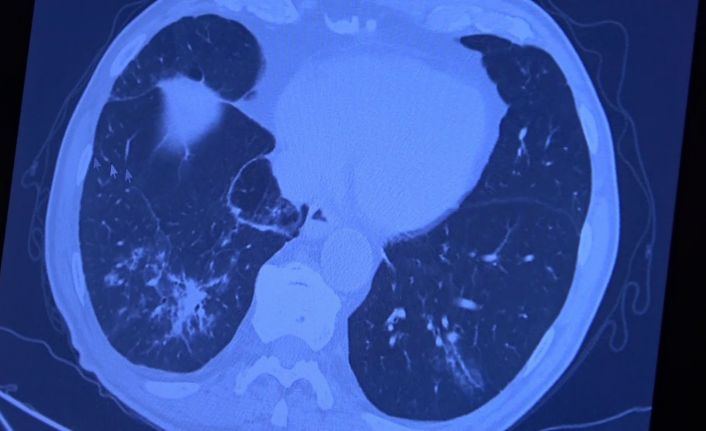

Korona virüs hastalığı genç nüfusta daha fazla görülmeye başlarken Covid-19 aşıları tamamlanan 60 yaş üstü vatandaşlardan bazıları ise korona virüse yakalanmaya devam ediyor. VM Medical Park Samsun Hastanesinde görev yapan Göğüs Hastalıkları Uzmanı Prof. Dr. Şevket Özkaya ise aşının gerçek yaşam sonuçlarını gözler önüne serdi. 2. doz aşıları tamamlanmış fakat Covid-19 servisinde yatan hastaların akciğer tomografilerini inceleyen Prof. Dr. Özkaya, bu kişilerin akciğer tutulumları olduğu halde hastalığı hafif atlattıklarını söyledi.

Bugüne kadar aşının etkilerini hep laboratuvar ortamında antikor üretip üretmemesi ile değerlendirdiklerini belirten Prof. Dr. Özkaya, "Vatandaşlarımız aşılarını olduktan sonra ilk gerçek yaşam sonuçlarını yeni yeni almaya başladık. Gerçekten aşı yaptığımızda antikor oluşturuyor ama bu antikor kişiyi koruyacak mı diye merakla beklediğimiz sorunun cevabını, insanlar 2. doz aşısını olduktan bir ay sonra ortaya çıkmaya başladı. Bu hastalar korona virüsü kaptığında yeni yeni korumaya başladığını anladık. Bir örnek vermem gerekirse, 84 yaşında bir hastamız 2. doz aşısını olduktan sonra eşiyle beraber Covid-19 oluyor. Korona virüsü akciğer tutulumları olduğu halde çok hafif şekilde atlattılar. 65 yaşında başka bir hastamızı göstermek gerekirse, bu hastamız da 2. doz aşısını olmuş ve aradan 1 ay geçtikten sonra antikor da oluşmuş. Bu antikor bu kişiyi koruyacak mı diye gerçek yaşam sonuçlarına baktığımızda, koronanın hastanın akciğerlerine indiği halde çok hafif atlattığını görüyoruz. Eğer bu kişi aşı olmasaydı, hastaneye yatarak daha ağır geçirebilirdi" diye konuştu.

Covid-19 servisinde yatan hastaların yüzde 80’inin gençlerden oluştuğunun altını çizen Prof. Dr. Özkaya, "Artık daha genç hastaların mutant virüsle karşılaştıkları için daha ağır geçirdiği görüyoruz. 60 ve 65 yaş üstünü ise aşıyla sigortaladığımızı düşünüyoruz. Aşının gerçek yaşam sonuçlarının olumlu olduğunu görüyoruz. Aşı olanlar virüse yakalandıkları halde çok hafif veya hastaneye yatmadan atlatıyorlar. Şu an servisimizde yatan hastaların yüzde 80’inini genç hastalar oluşturuyor. Artık 60 yaş üstünde çok fazla hasta görmüyoruz. Örneğin (akciğer filmini gördüğümüz) 40 yaşındaki bir hastamız aşılanmadığı için mutant virüse yakalanmış. Akciğerleri çok kötü durumda ve hastanede yatıyor. 24 yaşında bir genç kızımızda ise ciddi akciğer tutulumları görüyoruz. 49 yaşında bir hastamızı ise maalesef çok ciddi akciğer tutulumu ve neredeyse paramparça bir akciğerle yoğun bakımda takip ediyoruz" şeklinde konuştu.